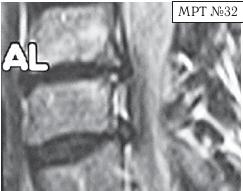

МРТ № 3

На МРТ № 3 — поясничный отдел позвоночника. (На данном «контрольном» снимке наблюдаются остаточные явления дегенеративно-дистрофического процесса в сегменте LV-SI после устранения методом вертеброревитологии секвестрированной грыжи межпозвонкового диска.)

В поясничном отделе форма позвоночного канала, создаваемая телом и дужками позвонка, вариабельна, но чаще она пятиугольная. В норме позвоночный канал в пояснично-крестцовом отделе сужен в переднезаднем диаметре на уровне LIII и LIV позвонков. Его диаметр каудально увеличивается, и поперечное сечение канала приобретает форму, близкую к треугольной, на уровне LV-SI. У женщин канал имеет тенденцию к расширению в нижней части крестцовой области. Сагиттальный диаметр значительно уменьшается от LI к LIII почти неизменен от LIII к LIV и увеличивается от LIV к LV. В норме переднезадний диаметр позвоночного канала в среднем равен 21 мм (15–25 мм).

Существует простая и удобная формула определения ширины позвоночного канала:

нормальный сагиттальный размер не менее 15 мм;

11–15 мм — относительный стеноз;

менее 10 мм — абсолютный стеноз. Уменьшение этого соотношения свидетельствует о сужении канала.

Высота поясничных межпозвонковых дисков 8–12 мм, нарастает от LI до LIV-LV, обычно уменьшается на уровне LV-SI